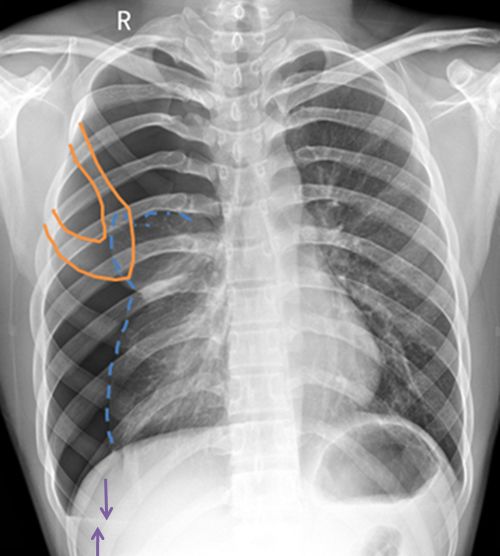

病例3患者的X线胸片

右上肺野见异常透亮无肺纹理区,内缘可见发线状肺组织压缩边缘,肺叶被压缩约30%(蓝色箭头)。心影及纵隔向对侧轻度移位(蓝色直线)。两膈面光滑,肋膈角锐利。